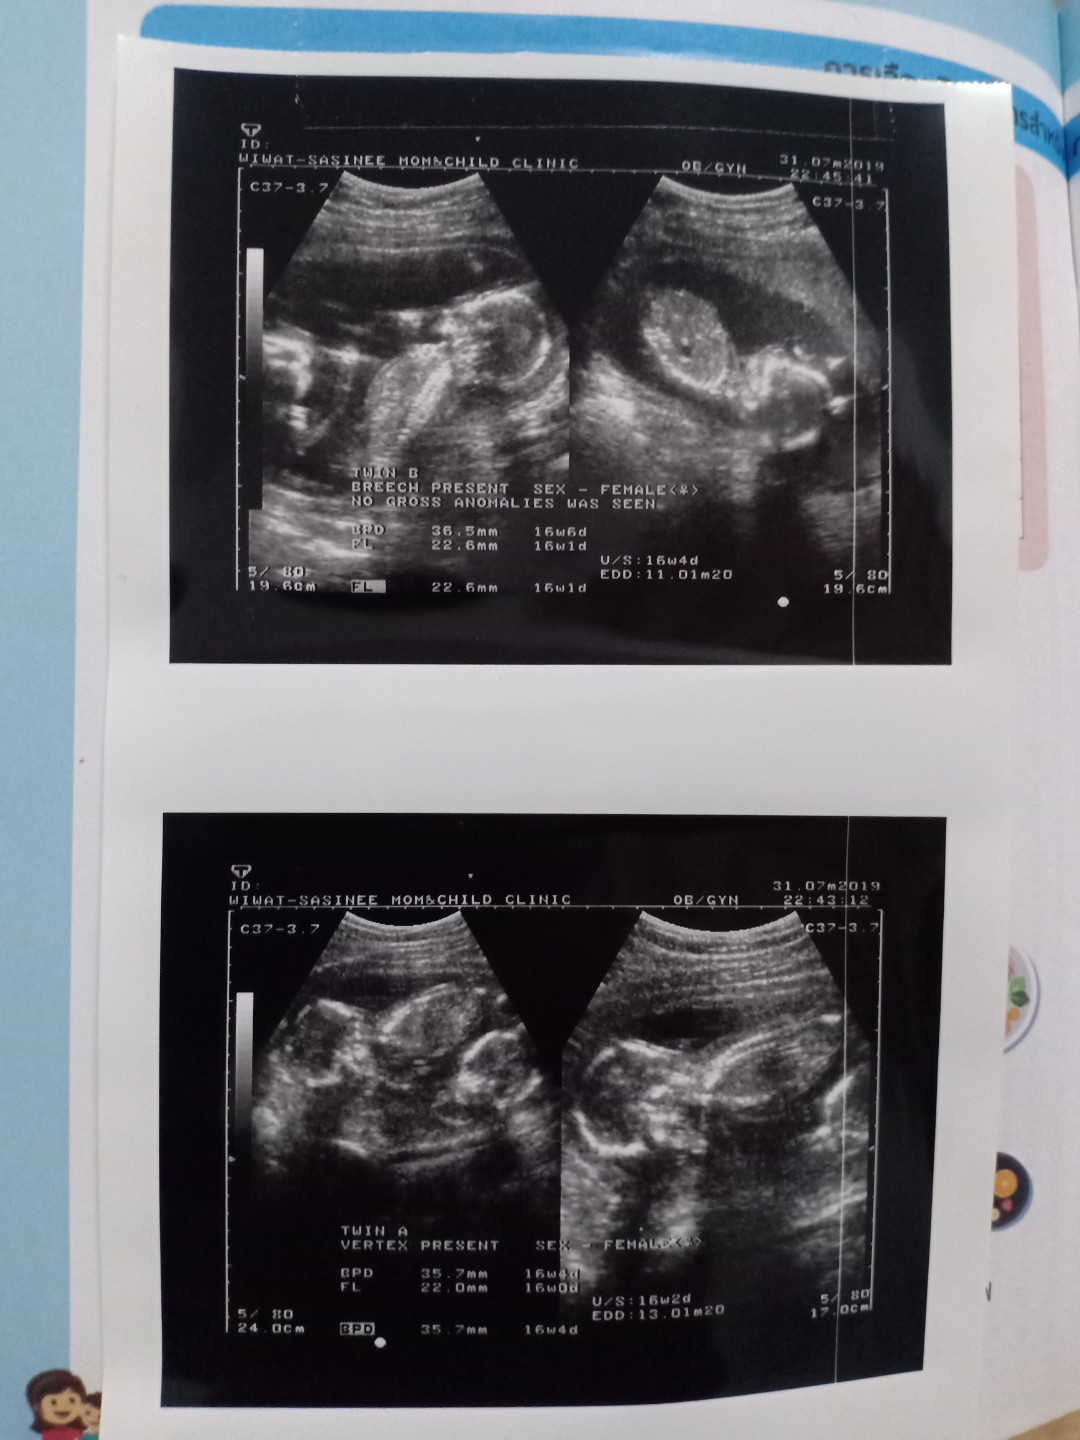

16w 4d แฝดหญิง😍